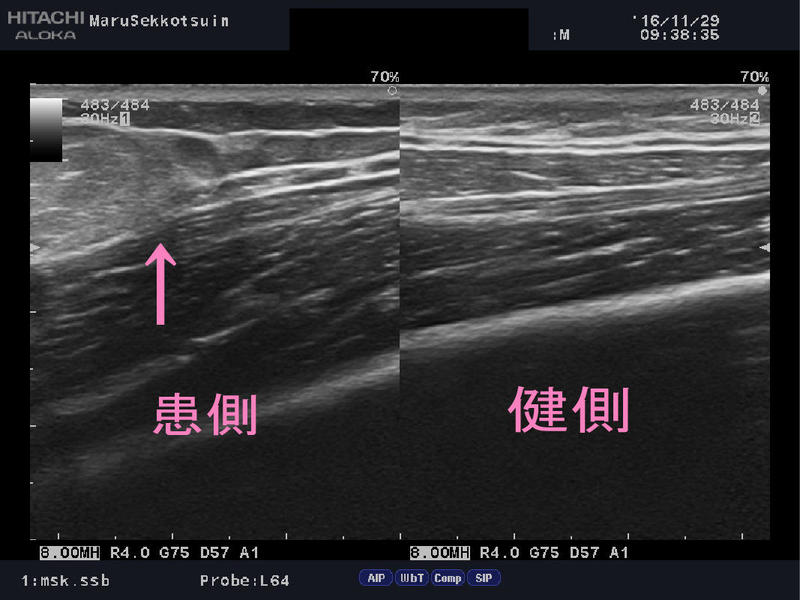

エコー検査の結果。

「上腕三頭筋外側頭断裂」

上腕三頭筋の断裂は非常に稀です。

場所を問わず筋肉・腱が断裂したら激痛のはずです。

憶えがないことや、触診しても疼痛誘発テストをしても、

痛みが出ないことから、加齢による変性断裂と判断し、

筋力については、右の健側の上腕三頭筋より少し弱いですが、

目に見える低下はなく日常生活には問題がないレベル。